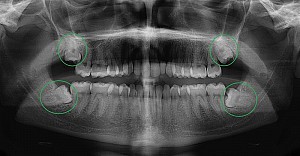

Hình ảnh răng khôn mọc lệch

Hình ảnh chụp X-quang bệnh nhân mọc răng khôn